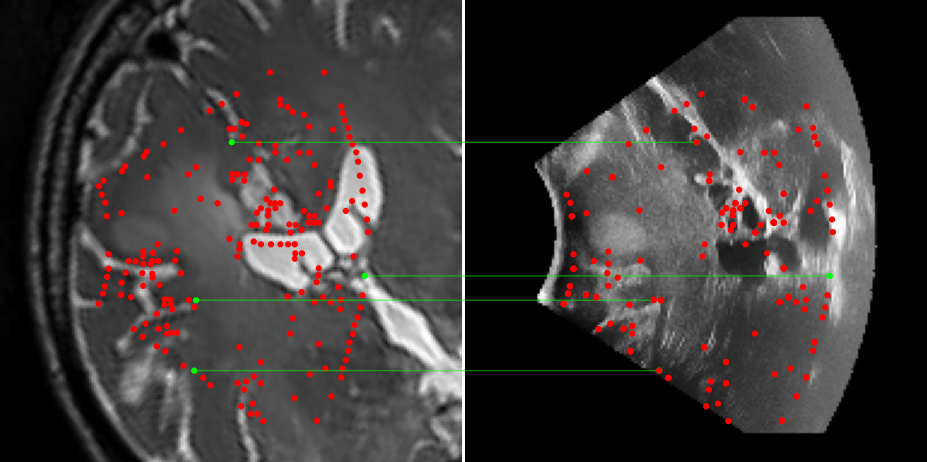

Figure 3: Examples of matching on three cases, one per column (MR on left and US on right). From top to bottom: SIFT+Cosine, MIND+Cosine, SP+Cosine, SP+LG, Ours+LG, Ours+Cosine. Correct matches recovered by each method are shown in green lines and mismatched are shown with a red dot.

To evaluate the performance of our model against existing image methods, we compared it to three approaches: SIFT [16], which remains the standard for keypoints matching, SuperPoint (SP) [3] built using a self-supervised learning approach and MIND [10], a modality-invariant descriptor for medical imaging, that although not designed for 1-to-1 keypoint matching, is extensively used for multimodal medical image registration through grid regularizing. We use SIFT and SP as keypoints detectors and descriptors, while we combine MIND with SP keypoints since it only provides a descriptor. We match these descriptors using both Cosine similarity and the deep neural network LightGlue (LG) [15] when possible (SP and Ours). Results reported in Table 2 and shown in Fig. 3 show that our approach outperforms these methods in terms of matching score, precision, and number of matched points. We only report results on three cases for readability reasons. Associating our descriptor with Cosine and LG reached similar performance depending on the metric.